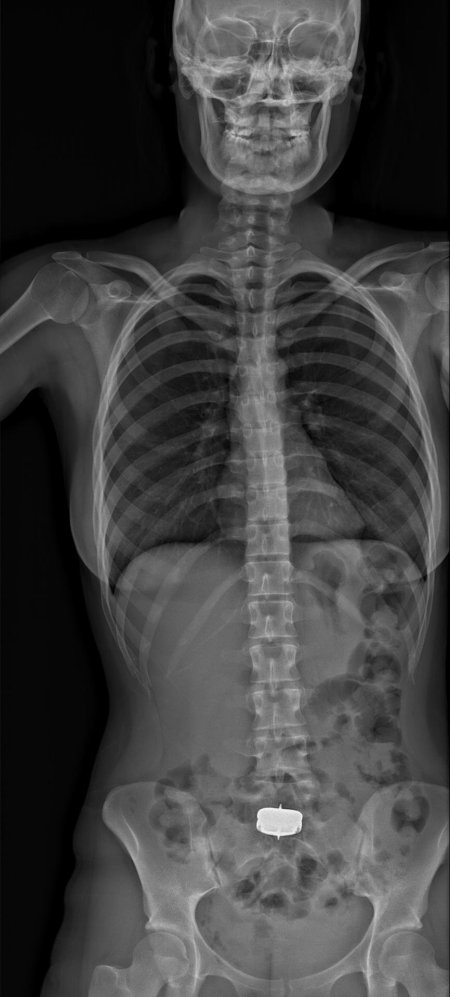

Рентгеновский эффект создает фантастические композиции в этих фотографиях девушки, чье тело становится прозрачным, демонстрируя скелет и внутренние органы. Она позирует в разных позах, ее силуэт светится загадочным свечением. Каждый кадр передает атмосферу научной фантастики и медицинского искусства. Ее кожа кажется полупрозрачной, позволяя увидеть кости и мышцы. Фотографии рассказывают о хрупкости человеческого тела и его внутренней красоте. Девушка то стоит в задумчивости, то делает грациозное движение. Эти иллюстрации вдохновляют на размышления о человеческой анатомии и уязвимости. Каждая картинка - это момент прозрения, когда внешнее уступает место внутреннему. Девушка воплощает образ современной Медузы, сочетающей красоту и загадочность.

Сквозь материю: тайны анатомии